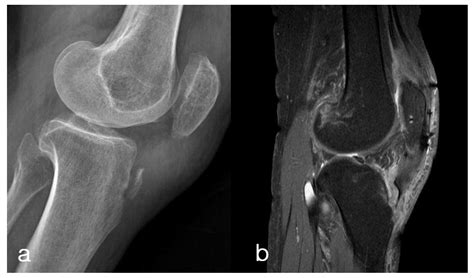

To confirm the diagnosis, medical professionals typically utilize imaging studies. X-rays are the gold standard for visualizing the displaced bone fragment and determining the severity of the fracture. In more complex or comminuted cases, an MRI may be ordered to assess the condition of the surrounding soft tissues, including the patellar tendon and menisci.

Orthopedic surgeons often categorize these injuries based on the Ogden classification system, which helps guide treatment decisions. This classification ranges from simple, non-displaced fractures to complex injuries that extend into the knee joint.

Type Severity Description Typical Treatment

Type I Small fracture at the distal part of the tuberosity. Conservative (casting)

Type II Fracture extends through the secondary ossification center. Surgery often required

Type III Fracture extends into the articular surface of the knee. Surgical intervention